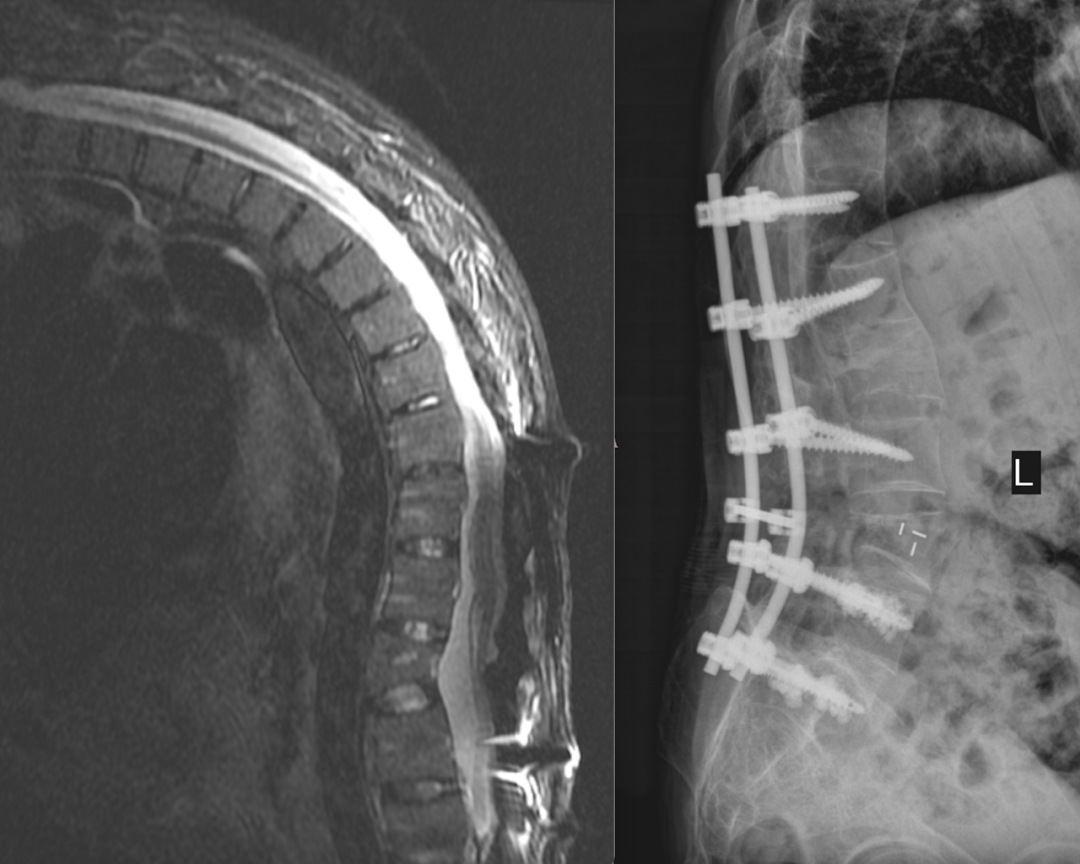

家礼医院骨科主任尹绍猛亲自为谢孟元接诊后,发现他的病情较为特殊:「患者是强直性脊柱炎晚期,出现了非常严重的后凸畸形,从片子上看达到了 90 度左右,由于患者已经做过一次手术,把整个腰背部的紧绷系结构都给破坏掉了,再次手术无疑会增加很大难度。」

因为患病时间长,患者逐渐形成了胸骨与耻骨联合相接触的「折刀样」畸形,再加上五年前在外院接受过一次矫形手术治疗,给手术治疗带来更大的挑战。

「传统的经椎弓根截骨矫正的度数在 15 度左右,但这位病人用传统的治疗方式效果不好,所以运用腰椎椎体的结构矫形手术,实现了 30 度的矫形。」尹绍猛说。

4 月 13 日,在经过充分的准备,并取得患者及家属同意后,骨科团队在麻醉手术团队的配合下,顺利为谢孟元进行了 「脊柱内固定取出术+后路腰 4 椎体后凸畸形经椎弓根截骨矫正、骨水泥椎弓根螺钉内固定术」。